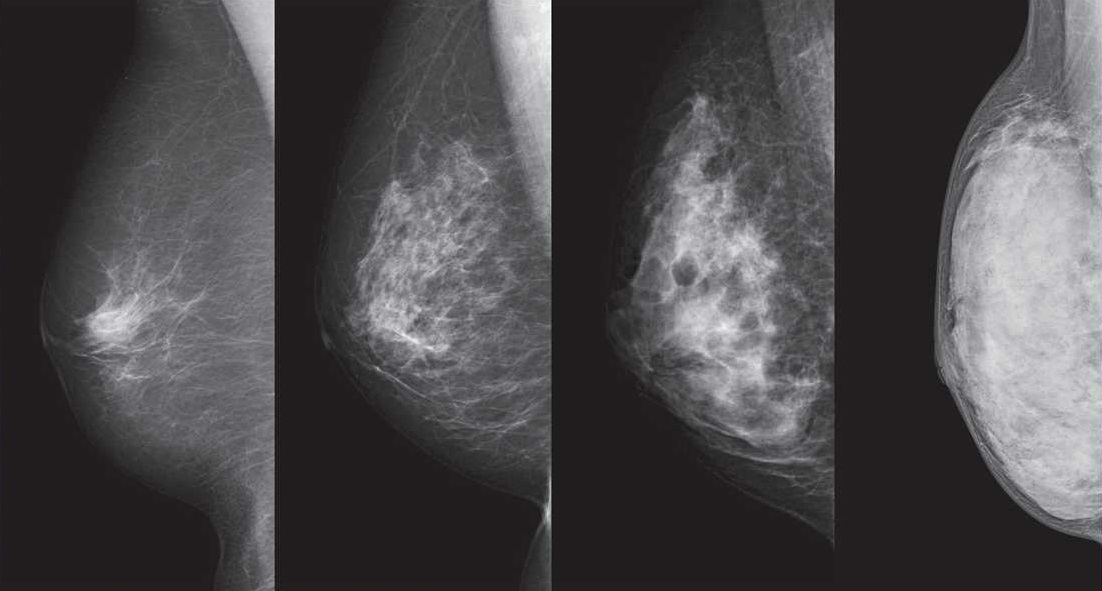

But experts in Japan remain divided — and undecided — on one issue surrounding breast cancer screenings and that is whether to tell people who undergo the tests if they have dense breast tissue.